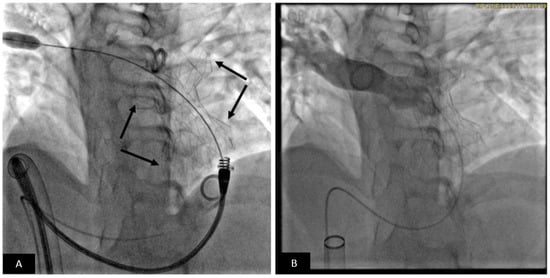

- Arar, Y.; Reddy, S.R.V.; Kim, H.; Dimas, V.V.; Zellers, T.M.; Abou Zahr, R.; Vamsee, R.; Greer, J.S.; Tandon, A.; Pontiki, A.; et al. 3D advanced imaging overlay with rapid registration in CHD to reduce radiation and assist cardiac catheterisation interventions. Cardiol. Young 2020, 30, 656–662. [Google Scholar] [CrossRef] [PubMed]

- Fagan, T.E.; Truong, U.T.; Jone, P.N.; Bracken, J.; Quaife, R.; Hazeem, A.A.; Salcedo, E.E.; Fonseca, B.M. Multimodality 3-dimensional image integration for congenital cardiac catheterization. Methodist Debakey Cardiovasc. J. 2014, 10, 68–76. [Google Scholar] [CrossRef] [Green Version]

- Ehret, N.; Alkassar, M.; Dittrich, S.; Cesnjevar, R.; Rüffer, A.; Uder, M.; Rompel, O.; Hammon, M.; Glöckler, M. A new approach of three-dimensional guidance in paediatric cath lab: Segmented and tessellated heart models for cardiovascular interventions in CHD. Cardiol. Young 2018, 28, 661–667. [Google Scholar] [CrossRef]